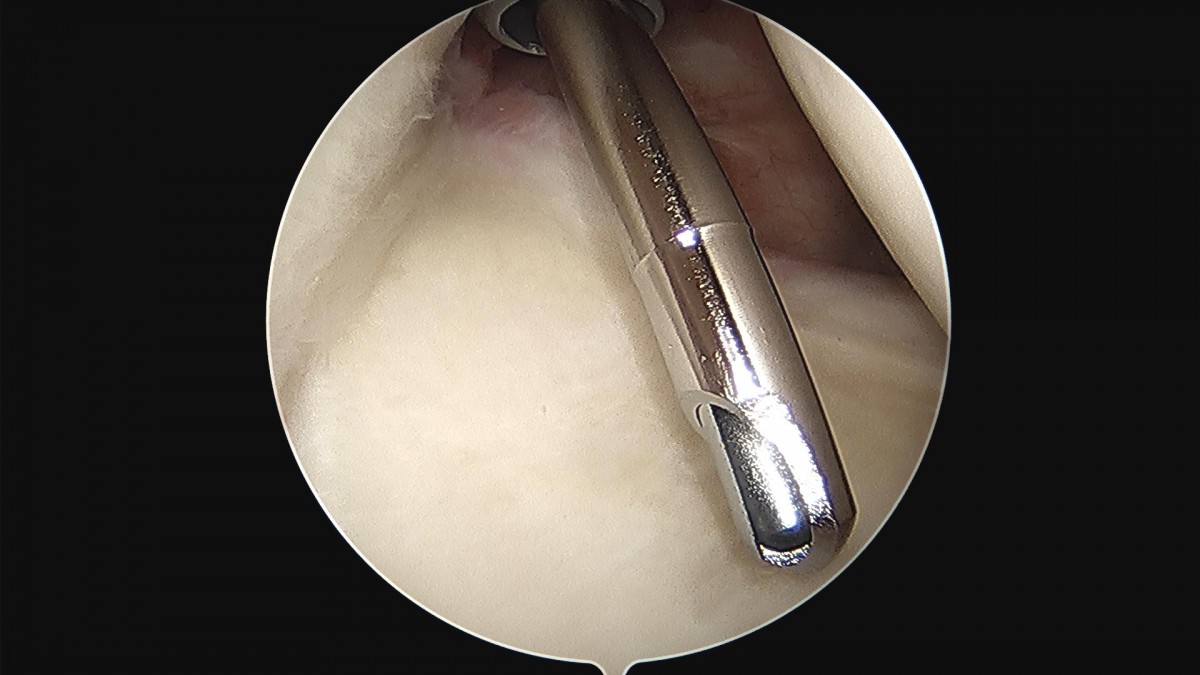

이재상 원장님 어깨 회전근개 봉합술 최기O 환자

d4279b3b94d98ed627b1644855bcf9f2_1699600592_1541.jpg